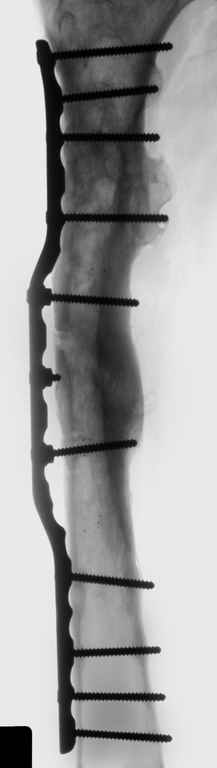

Операция выполнялась с помощью А.Н.Челнокова. Очень понравилась технология выполнения блокируемого остеосинтеза с использованием спицевого дистрактора, модифицированный гвоздь с латерализованным проксимальным отделом и возможностью многовинтовой фиксации проксимального и дистального участков бедра.